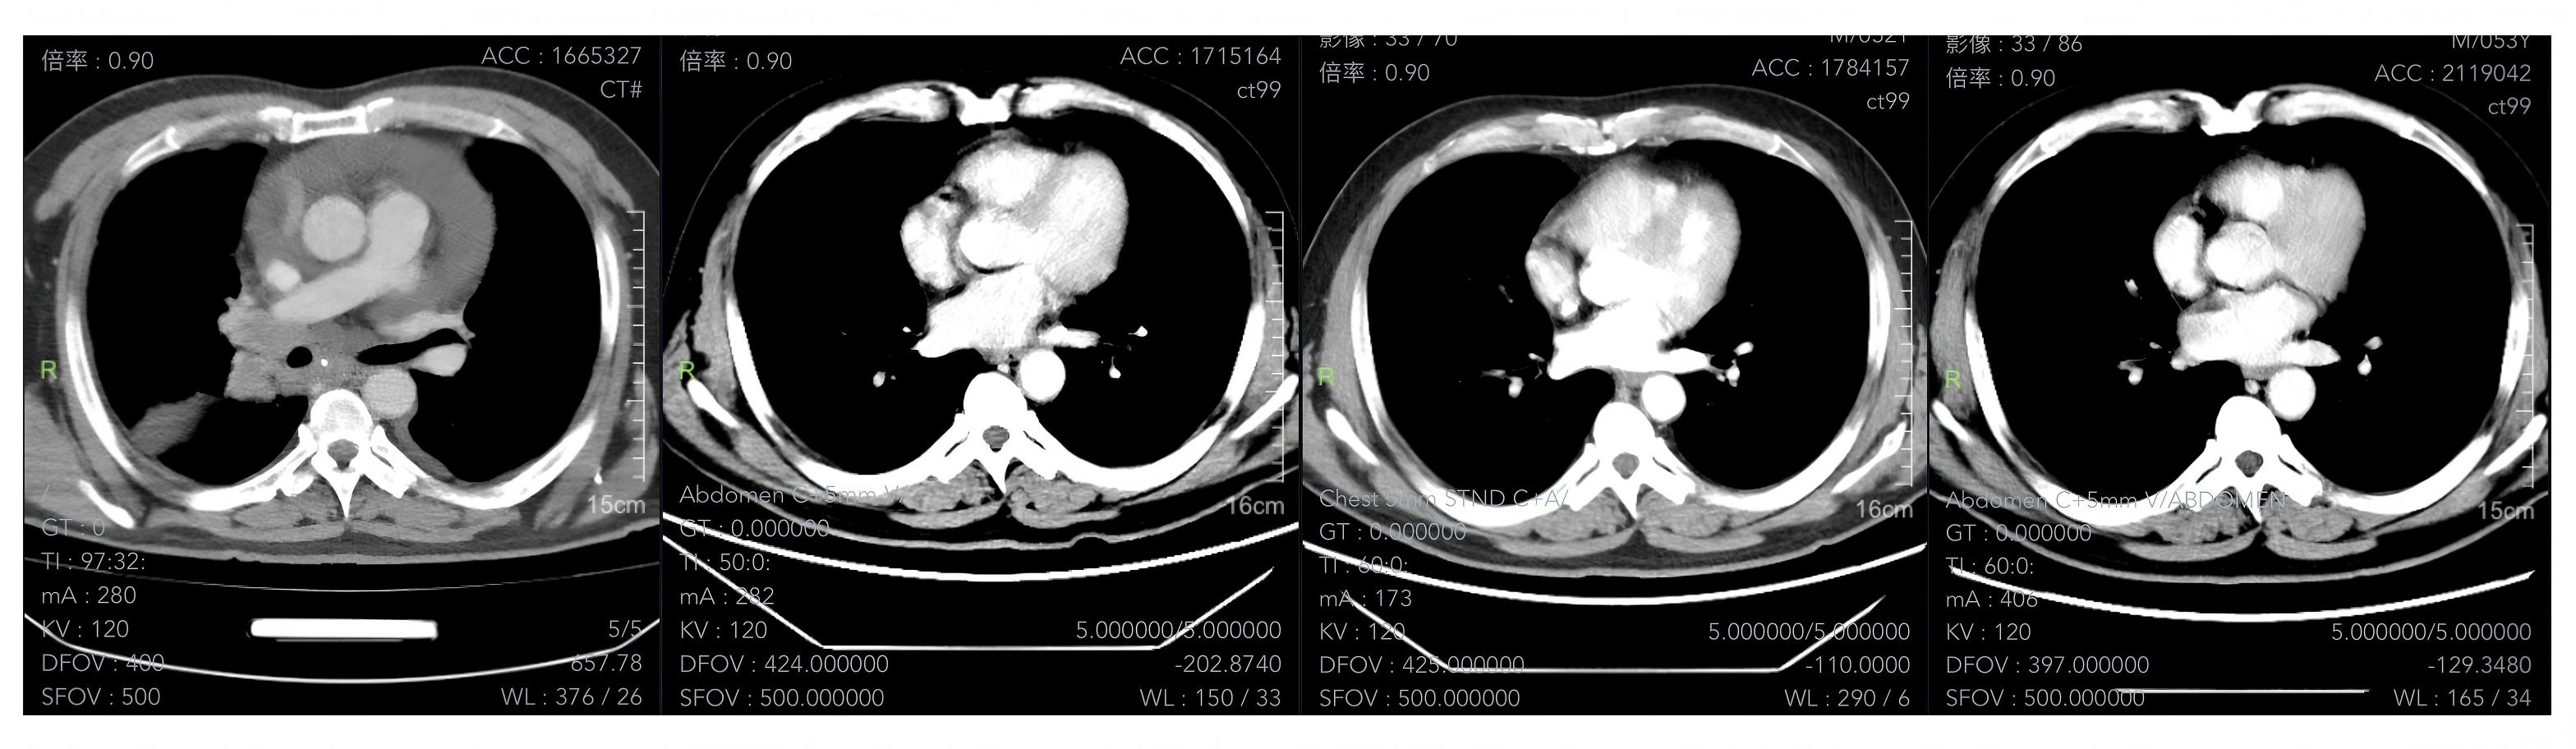

4、疗效评估:一线治疗2周期后疗效评估PR,6周期疗效评估达CR,患者肿瘤标志物持续降低,一线治疗1年及后期定期影像学复查,疗效评估维持CR。

影像学检查图像(基线、2周期、6周期、治疗1年后)